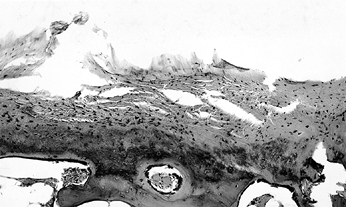

necrosis and is predicated on the disappearance of osteocytes from

within their lacunae, a process that takes several days to develop (Fig. 125.1).

![]() |

|

Figure 125.1. Necrotic bone and marrow from the center of the ischemic area (hematoxylin and eosin, ×50).